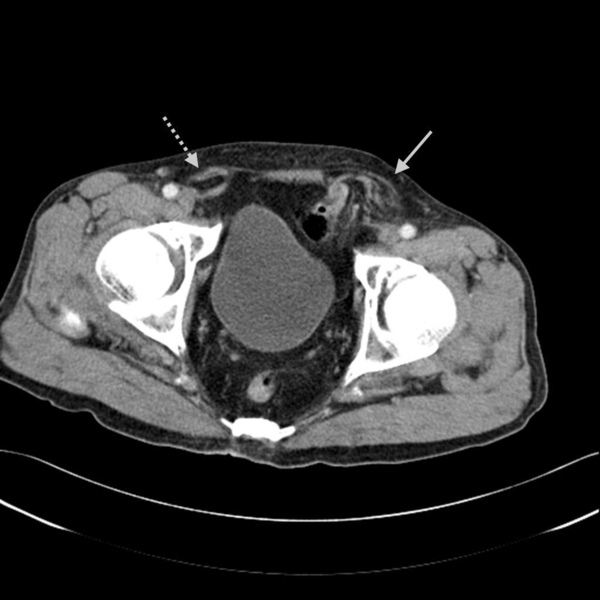

腹股溝疝氣又分為直接型(direct type)及間接型(indirect type)。上面這張圖恰好可以同時見到這兩型。灰色實心箭頭處是直接型(direct type),灰色虛線箭頭處是間接型(indirect type)。